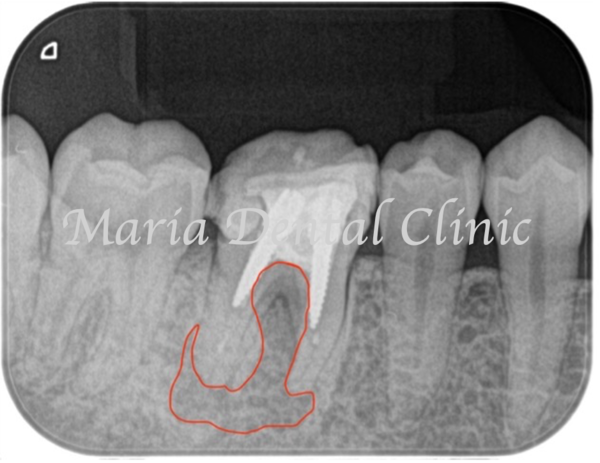

術前の写真を確認すると根の先端から広がる病変の影は歯の股の部分まで大きくなっていることが確認できます(術前写真②)

歯周病専門医による組織再生療法を行なった際にはレントゲンで透過像(黒い影)があった歯の股の部分の骨は著しく欠損していました(写真2術中)。骨の欠損部分に組織再生治療を行い、さらに3ヶ月の経過観察を行い生体の治癒を待ちました。